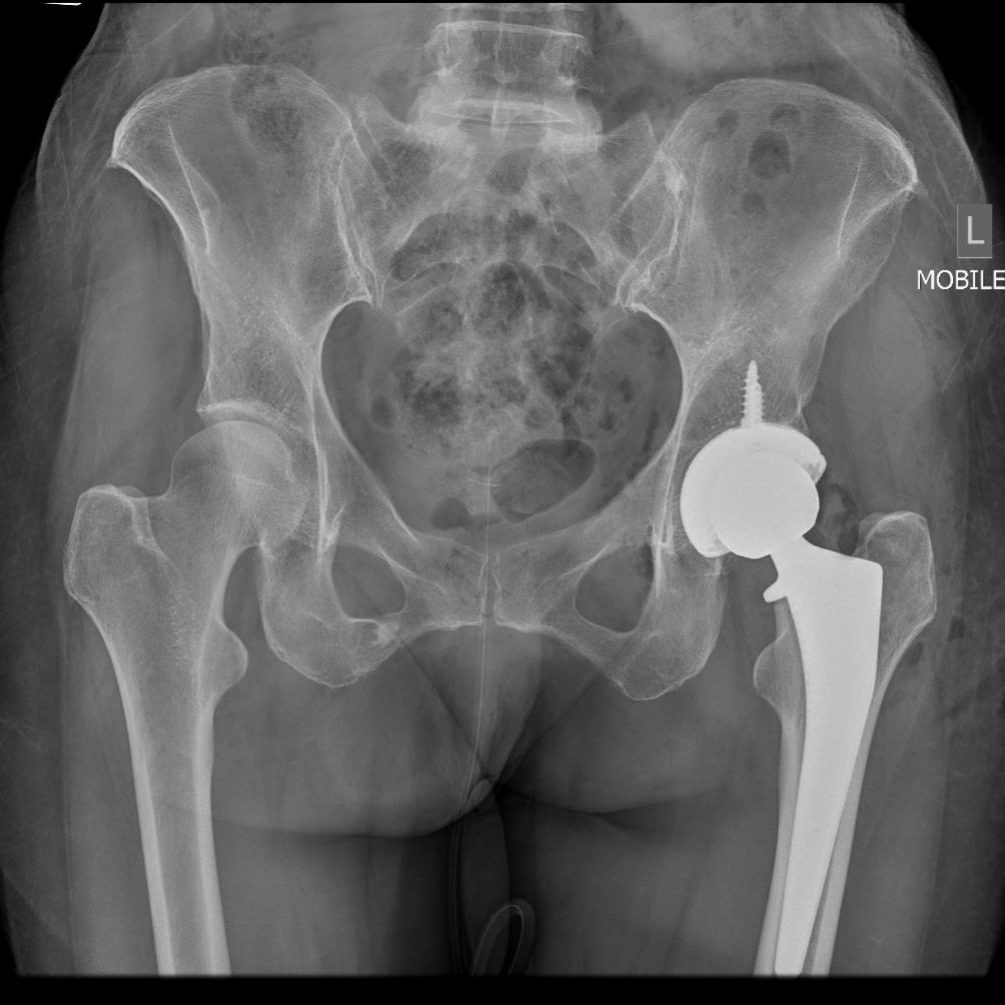

Hip Replacement Surgery

We specialize in full hip replacement surgery, offering both traditional and minimally invasive approaches. Our goal is to restore mobility and reduce pain, helping you get back to the activities you love.